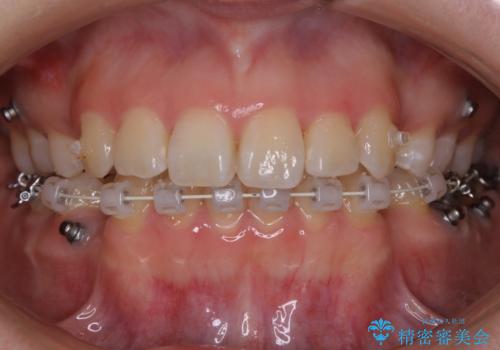

【抜歯】ハーフリンガル矯正で韓国美人な横顔へ!

- 前歯のガタつきと口元の改善を主訴に来院されました。

なるべく目立たない装置が良いというご要望と、口元を引っ込めたいというご要望を両方達成するために今回はハーフリンガル装置を選択し治療計画の立案を行いました。

結果的に表の装置よりは期間が掛かりましたが、口元もしっかり下がり韓国美人な横顔になったと患者様にも喜んでいただけました。

ハーフリンガル装置

ワイヤー矯正の中でも、上顎を裏側・下顎を表側に装置をつけて動かす方法をハーフリンガルといいます。

ハーフリンガルを選択すると、ワイヤー矯正の利点である抜歯ケースへの対応が可能な点と、表側の装置の欠点である装置が目立つという点をカバーして矯正治療を進めることができます。

表側の装置と違い、使えるワイヤーの種類に制限があり平均治療期間が長くなりやすい点、装置の作製自体の金額が掛かることから費用面で表側装置よりも高額になるという点はマイナスポイントであるといえますが、しっかりと口元を下げたり、噛み合わせの構築を行うことは遜色なく行えるため人気のある装置となっております。